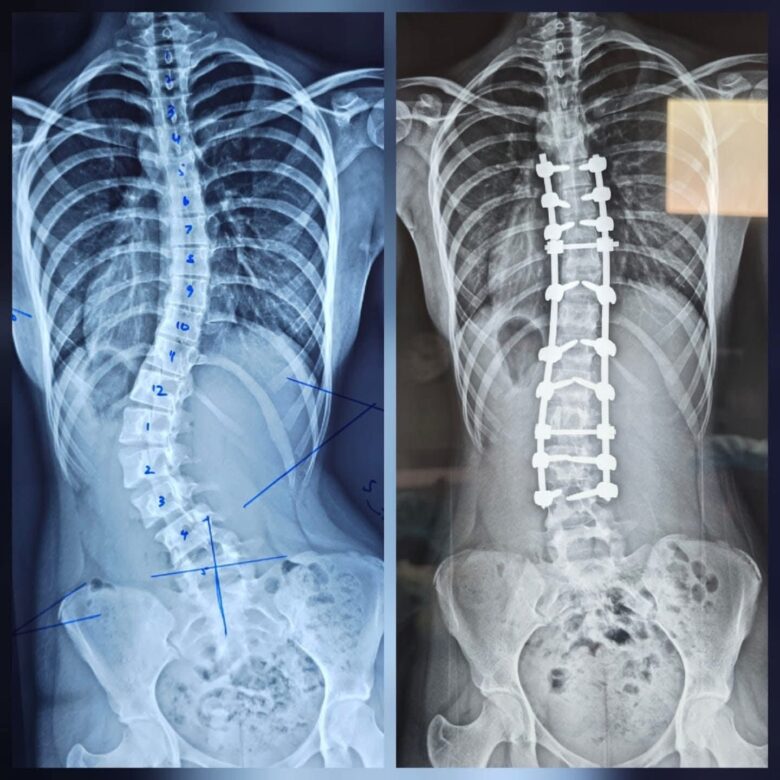

A scoliosis correction surgery was successfully carried out at Base Hospital Puttalam on March 25. This type of surgery is usually performed only in few hospitals such as those in Colombo, Kandy, Jaffna, Ratnapura and Badulla, making its performance in Puttalam noteworthy.

Although spinal surgeries have been conducted at this hospital over the past few months, this marks the first time that a scoliosis correction surgery has been performed at Base Hospital Puttalam.

This surgery, which typically costs over 4 million rupees, was provided completely free of charge. It is also significant to note that such a surgery has not previously been performed in Base Hospitals in Sri Lanka.